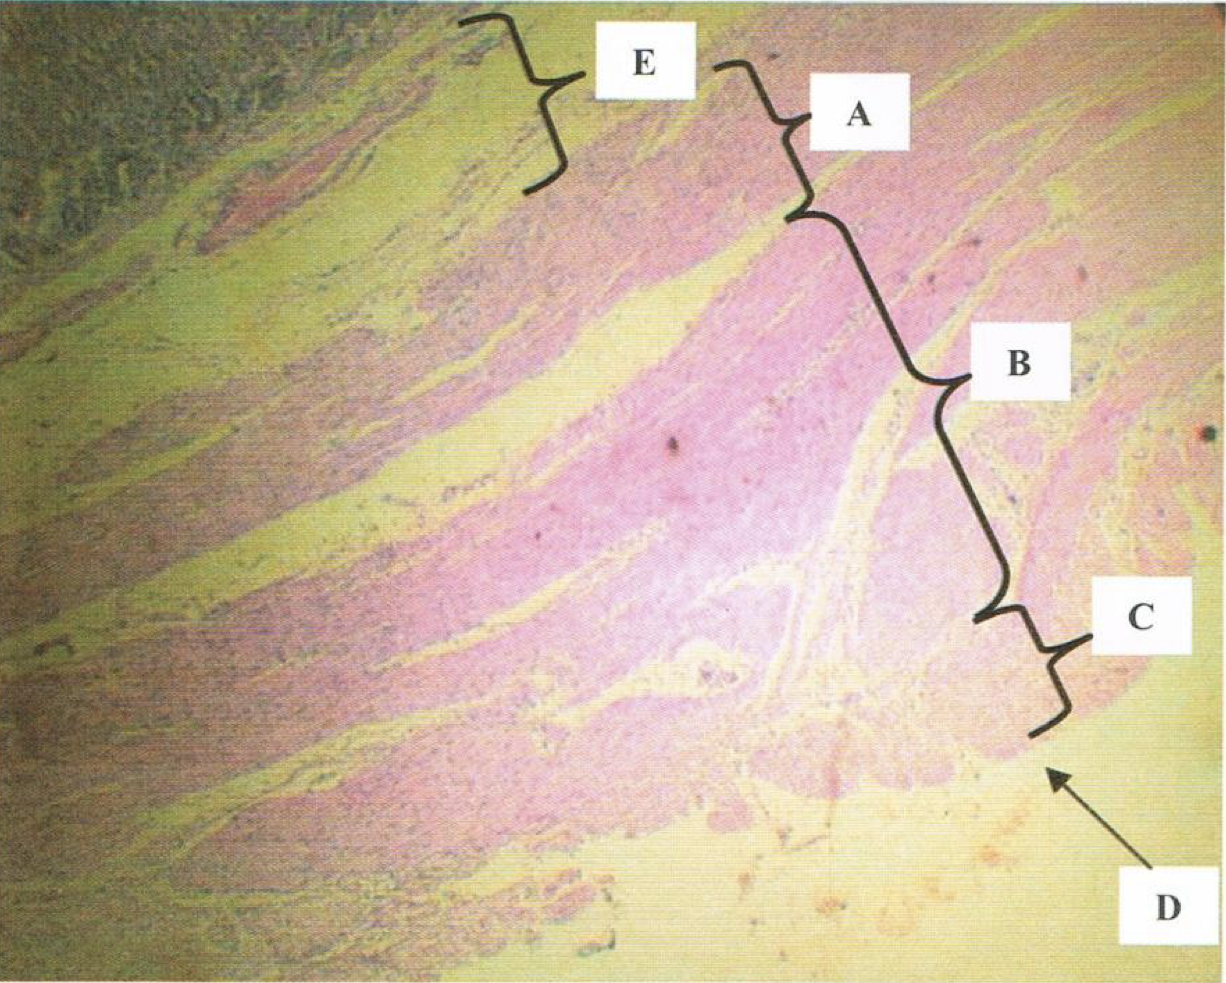

LPO view of STOMACH

E: submucosa

A: internal oblique

B: middle circular

C: outer longitudinal

D: tunica serosa/adventitia

Identify the structure